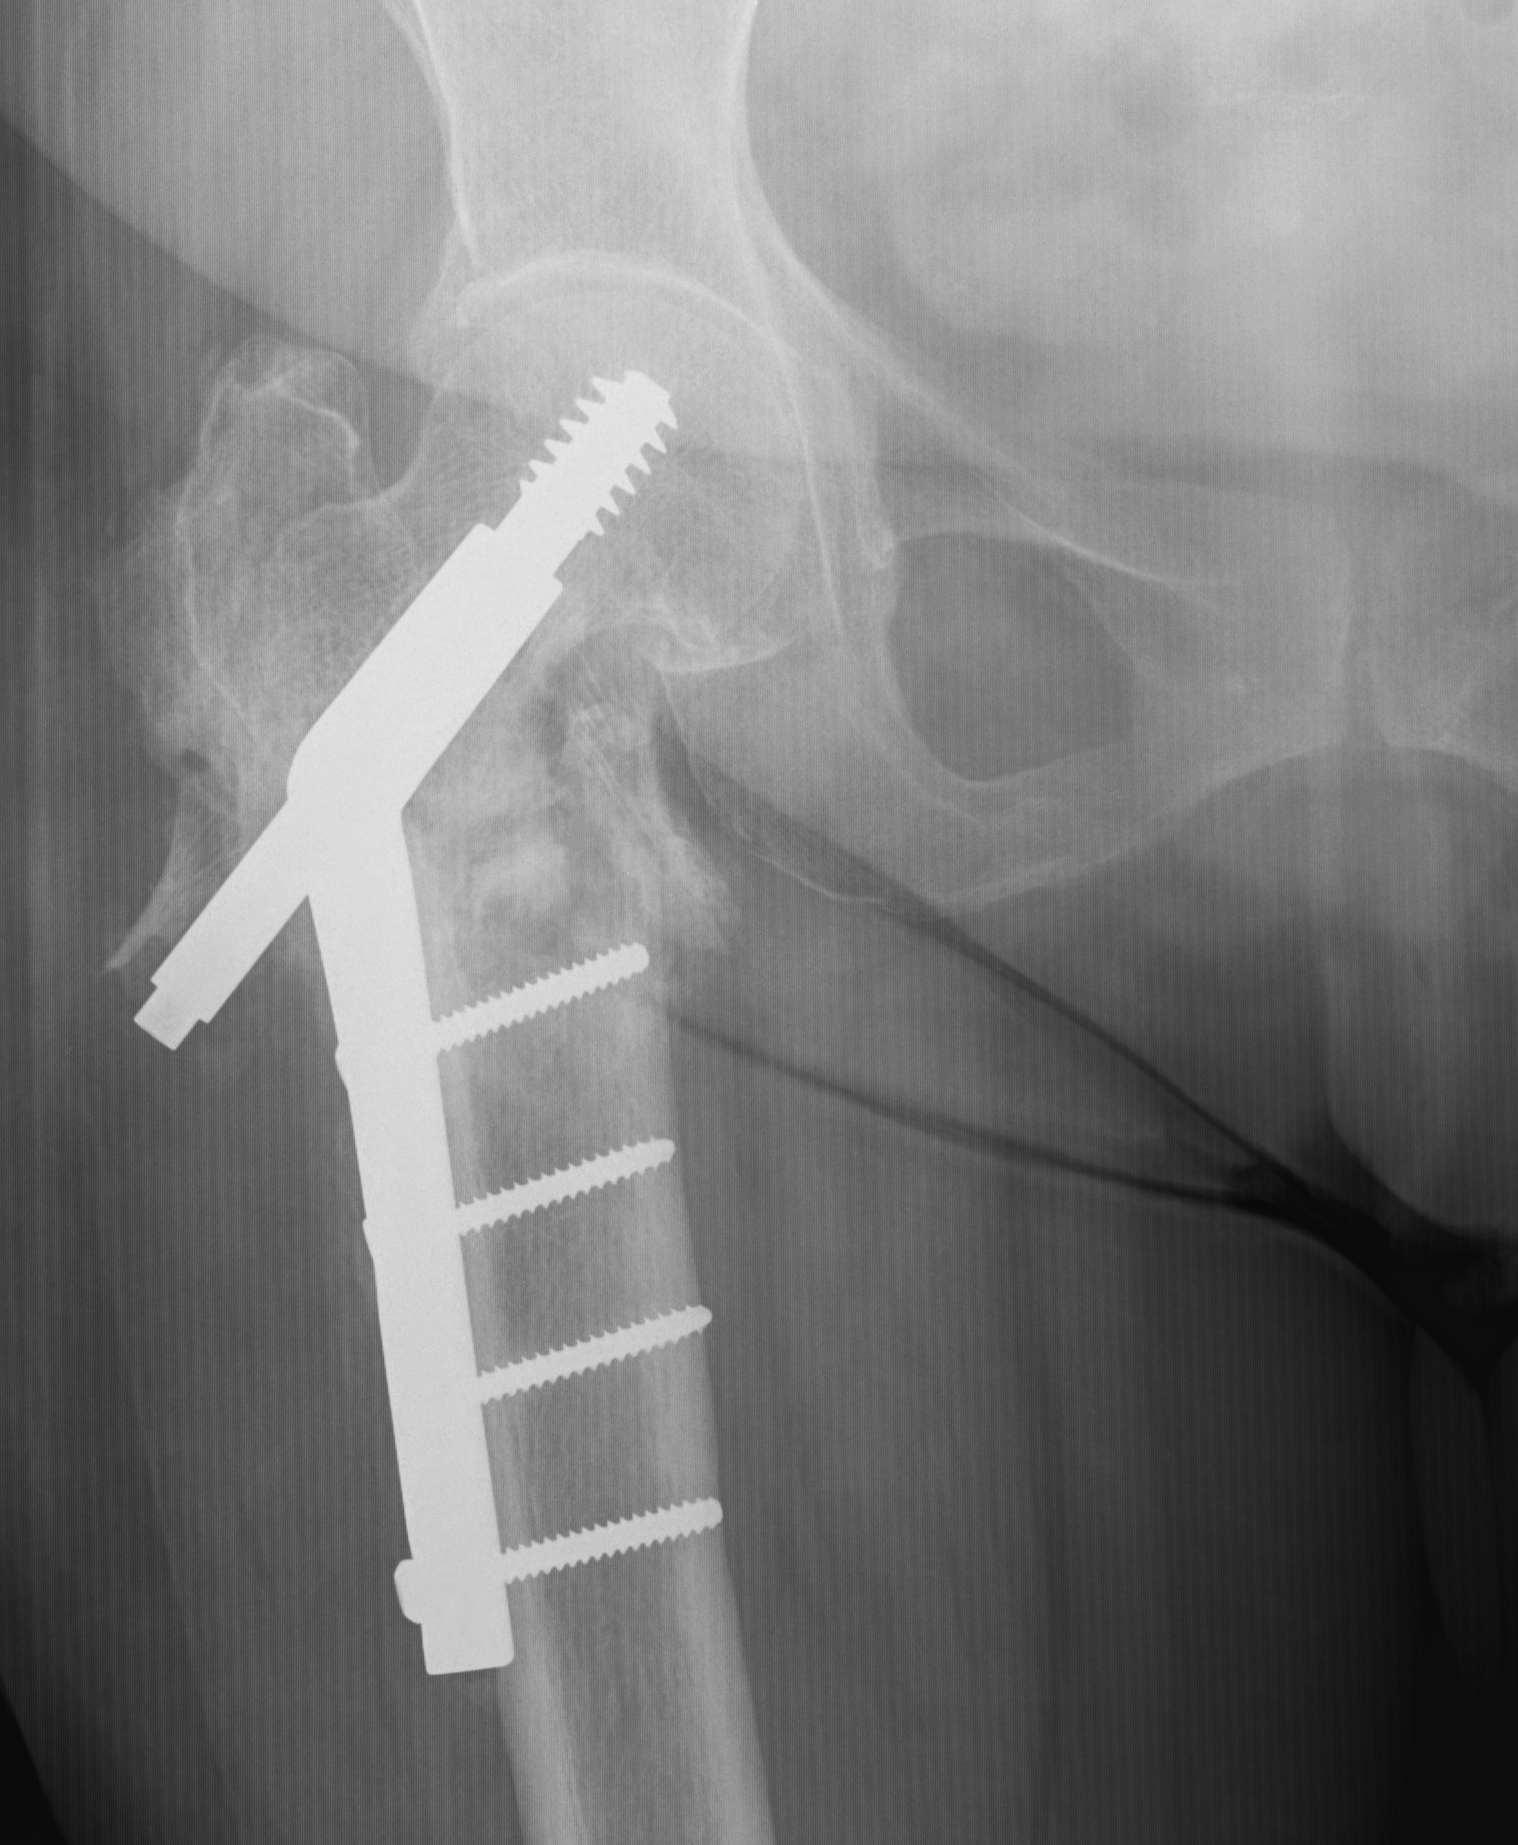

Sliding hip screw/dynamic hip screw

Dynamic hip screw

Mechanism

Plate is a lateral tension band whilst the sliding screw allows controlled fracture impaction

Technique

- traction table with anatomic reduction

- traction, adduction, internal rotation

Lateral approach to femur

- elevate vastus lateralis and control bleeding from perforators

Guide wire

- centred in femoral head in 2 planes

- tip-apex distance < 25 mm

Tip - apex distance

- from tip of screw to apex femoral head

- accumulative on AP and lateral

- > 25 mm, increases cut out

Measure angle

- wire in centre of neck / centre of head

- usually 130o prosthesis

Ream to within 5 mm of end of wire

- tap

- insert screw / tip apex distance < 25 mm

- attach plate

Options for improving stability

b. Trochanteric stabilization plate

Theory

- buttresses the GT and prevents lateral displacement